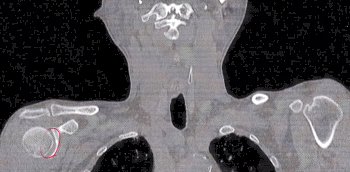

とりあえずCTスキャン。

で、頂きましたのが、その一部のこれらの画像なんです(^.-)☆

特に痛みの原因となるようなモノは見当たらず、強いて言えば『老化現象』との事でありました。